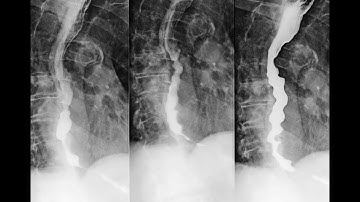

Diffuse oesophageal spasm